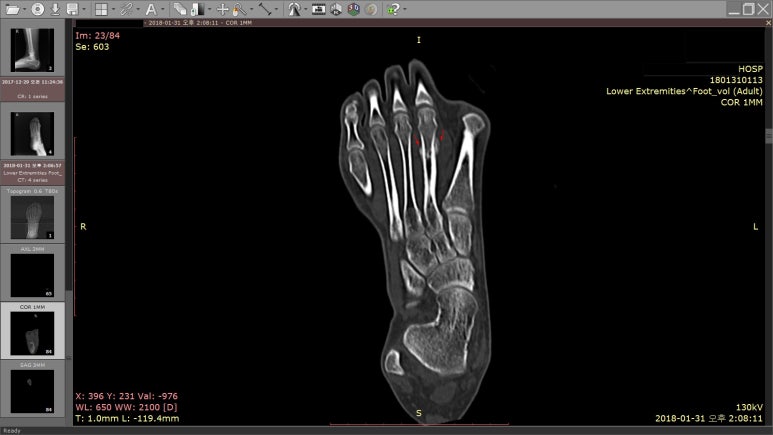

다시 찍어본 X-RAY에서

골절 후 흔적인 가골(bone callus)이 보였고,

정확하게 확인하기 위해 CT 검사를 받았습니다.

빨간 화살표로 표시한 부분이 발가락이 골절 됐던 곳입니다.